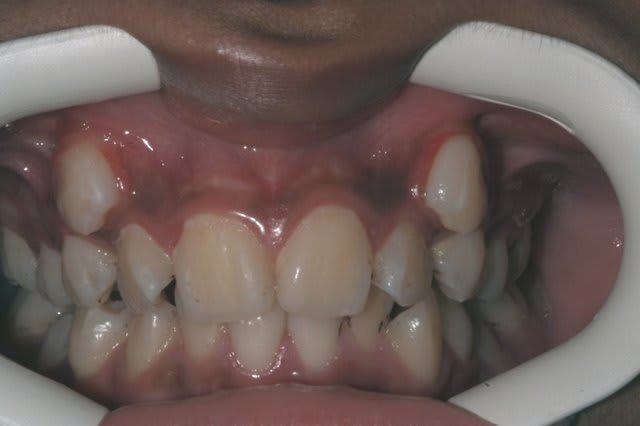

ou alors, on attends que ça devienne comme ça

Img 0477 k68wjf - Eugenol

ou encore comme ça!

à chaque fois, ça me hérisse quand les parents me répondent:

le dentiste m'a dit qu'il fallait attendre et que ça allait s'arranger

arrêter les les conseils d'autruche

Img 9861 ogyvix - Eugenol